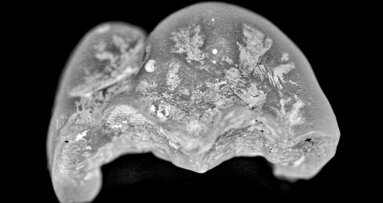

Regeneration of bone tissue could greatly benefit people with jawbone deficiencies due to tooth loss, infection or trauma. While an ideal method of ...